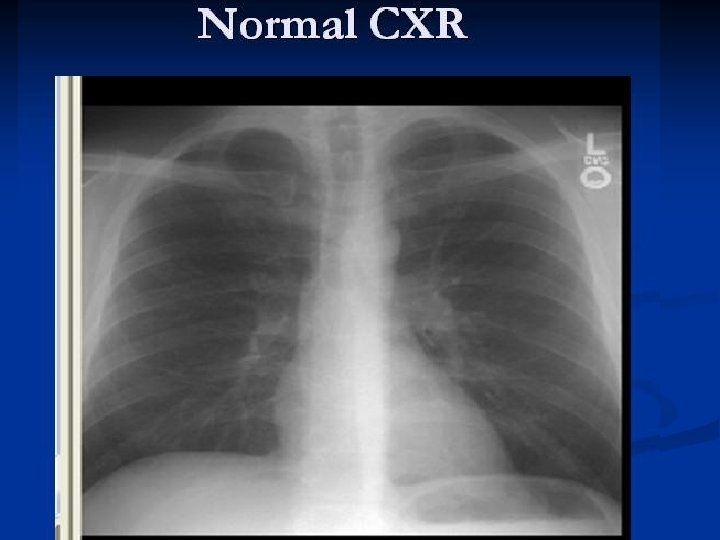

CXR n Acute : diffuse ground glass , fine nodular or reticulonodular pattern (lower lung ) n Subacute n Chronic : reticulonodular pattern : fibrosis , reticular opacity, honey combing n mediastinal lymphadenopathy (up to

Normal CXR